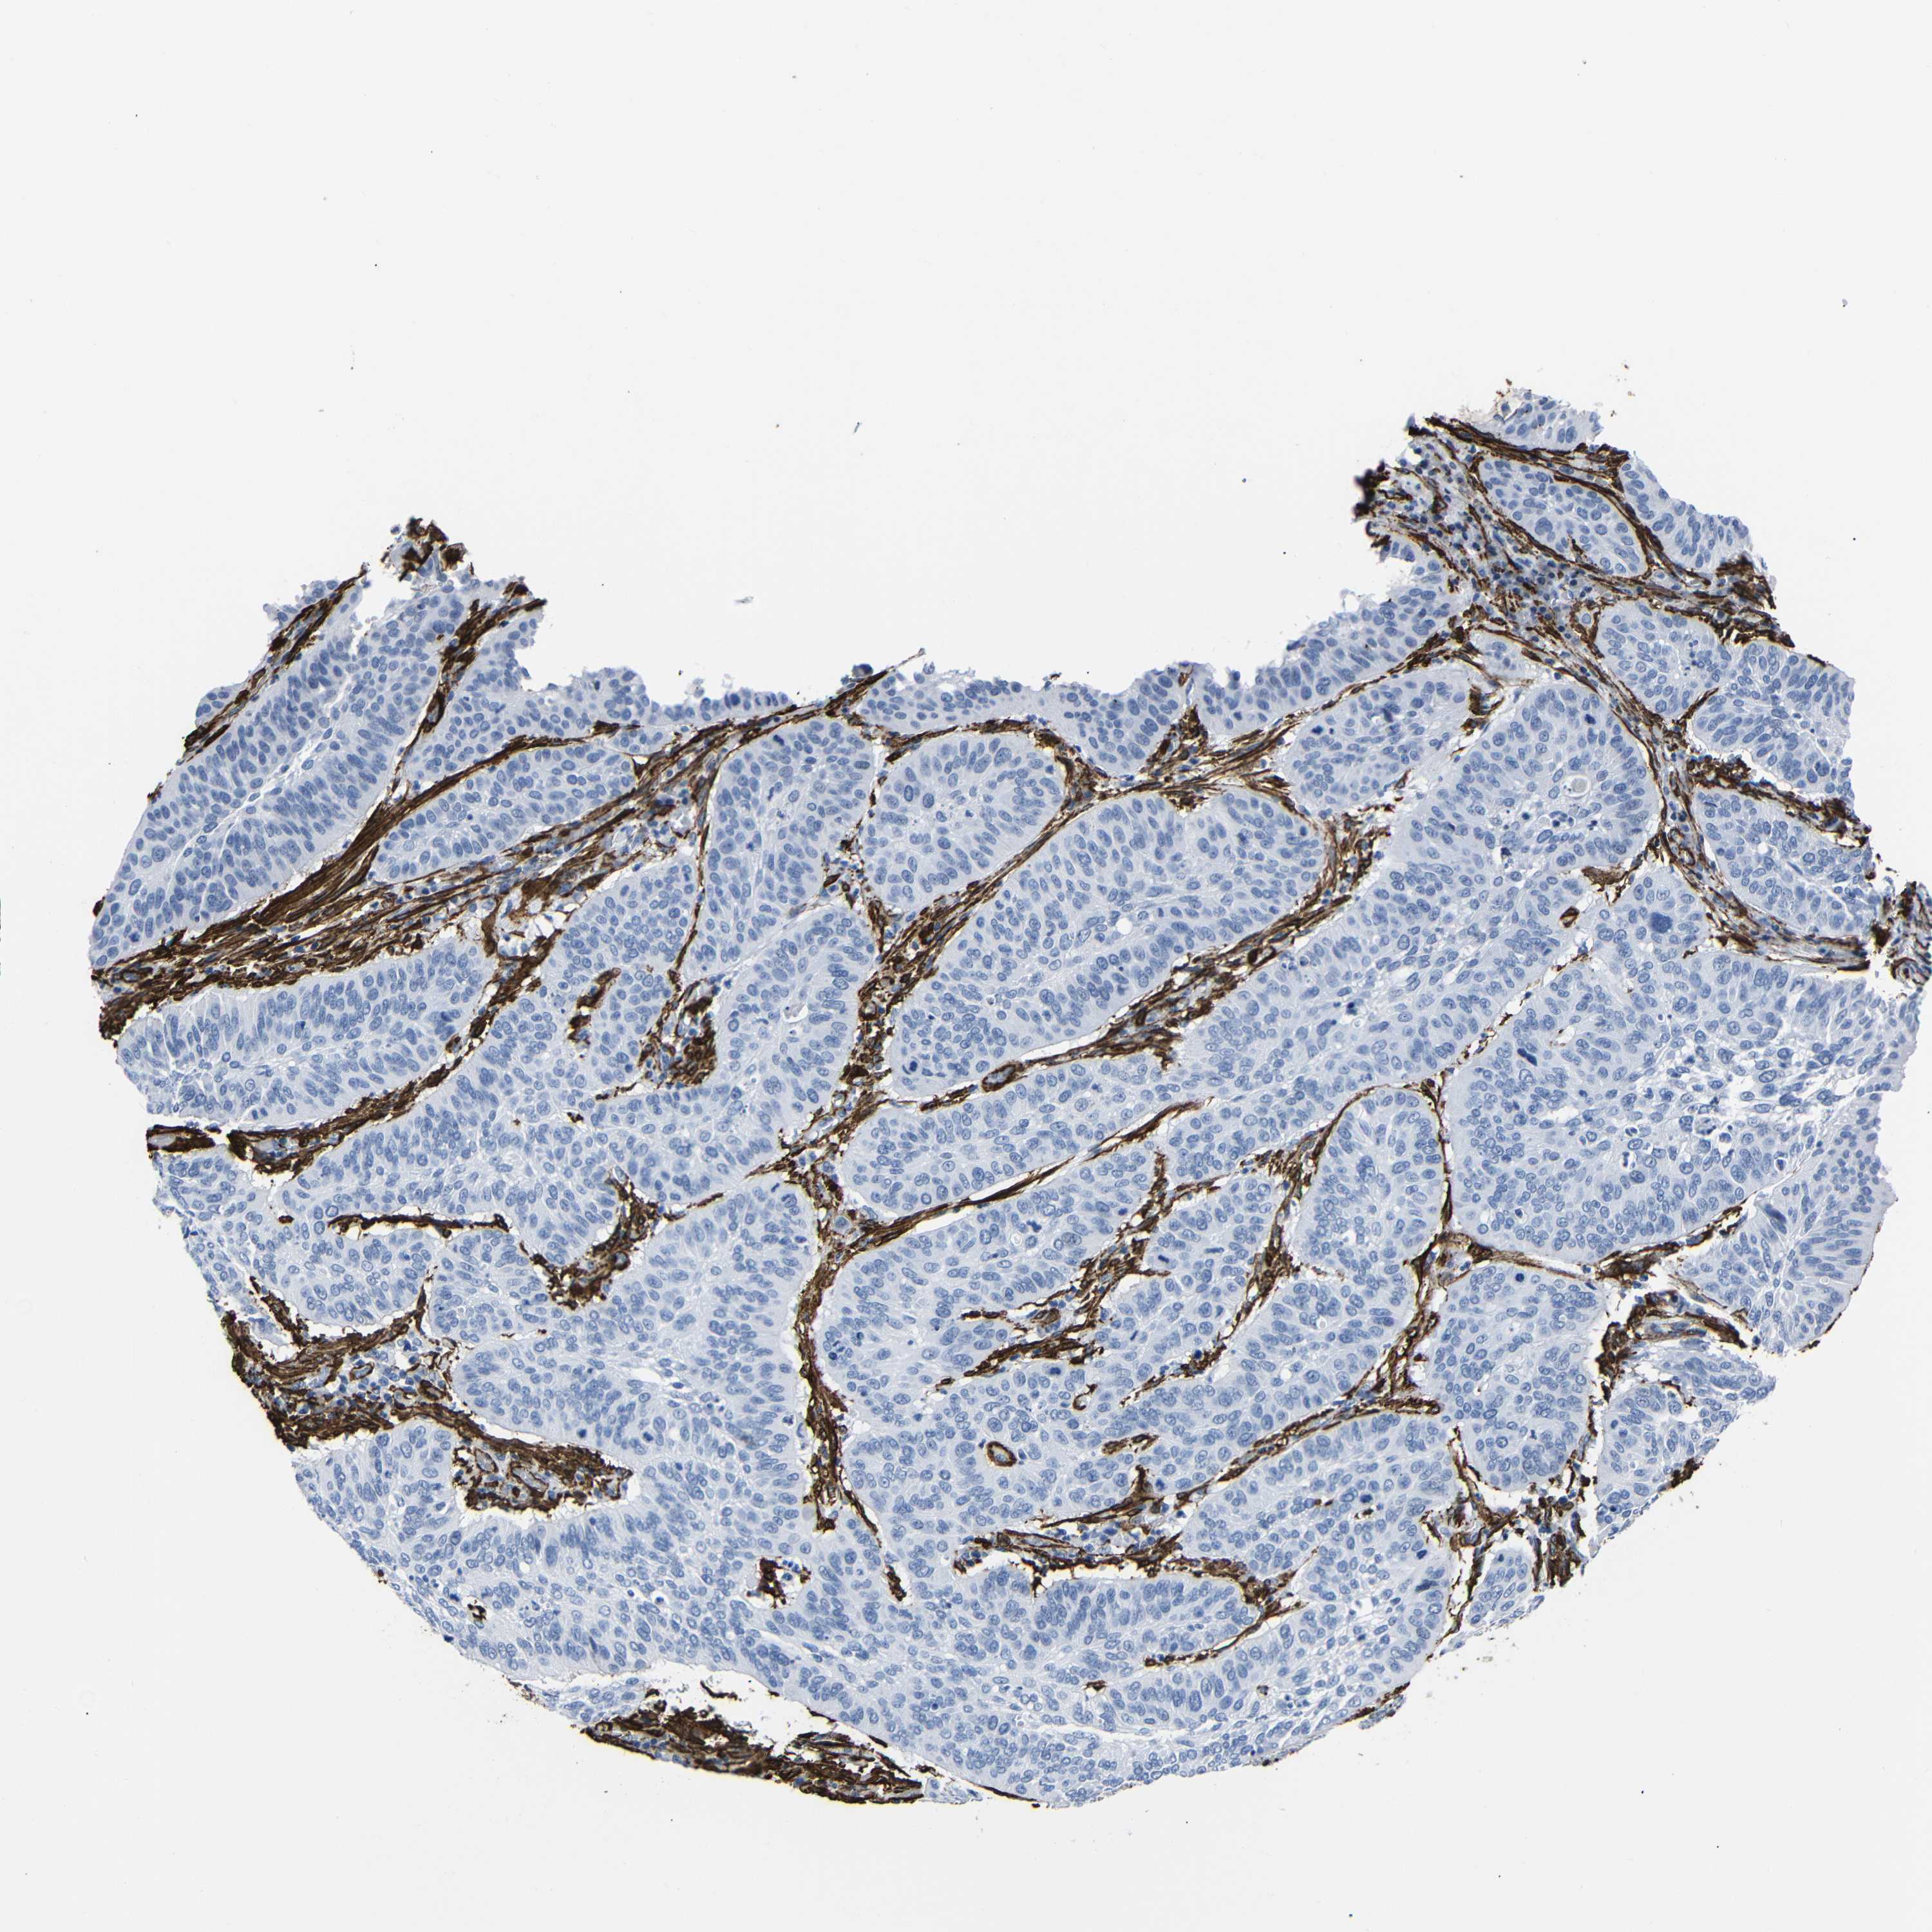

CERVICAL CANCER - Protein expressioni

A mouse-over function shows sample information and annotation data. Click on an image to view it in a full screen mode. Samples can be filtered based on level of antibody staining by selecting one or several of the following categories: high, medium, low and not detected. The assay and annotation is described here.

Note that samples used for immunohistochemistry by the Human Protein Atlas do not correspond to samples in the TCGA dataset.

Antibody stainingi

Antibody staining in the annotated cell types in the current human tissue is reported as not detected, low, medium, or high, based on conventional immunohistochemistry profiling in selected tissues. This score is based on the combination of the staining intensity and fraction of stained cells.

Each image is clickable and will lead to virtual microscopy that enables deeper exploration of all samples and also displays staining intensity scores, fraction scores and subcellular localization as well as patient and tissue information for each sample.

HPA041264

HPA041271

CAB000002

CAB003761

CAB013531

Staining

High

Medium

Low

Not detected

Intensity

Strong

Moderate

Weak

Negative

Quantity

>75%

75%-25%

<25%

None

Location

Nuclear

Cytoplasmic/membranous

Cytoplasmic/membranous,nuclear

Squamous cell carcinoma, NOS

Adenocarcinoma, NOS